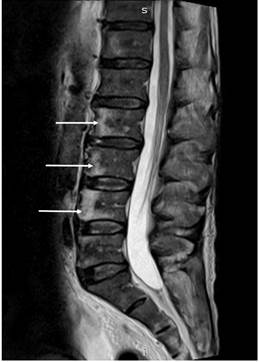

En la resonancia contrastada de la columna vertebral total se hallaron lesiones líticas en los cuerpos vertebrales L2, L3 y L4, y hueso ilíaco derecho con signos de reconversión medular (Figura 4). Durante la vigilancia clínica con cubrimiento antibiótico, se evidenció el deterioro clínico progresivo. Se realizó una colonoscopia en la que se evidenció una úlcera en la válvula ileocecal y el ciego, a la cual se le tomó una biopsia para realizar tinciones para hongos y reacción en cadena de la polimerasa (PCR) para tuberculosis. Ante el deterioro clínico con los hallazgos de múltiples órganos, se indicó el manejo con anfotericina B ante la sospecha de histoplasmosis, pero con niveles de galactomanano negativo, por lo cual se suspende al día 4 de manejo.

Figura 4 Resonancia magnética nuclear (RMN) de columna lumbar que evidencia lesiones focales de aspecto lítico en L2, L3 y L4 (flechas blancas).